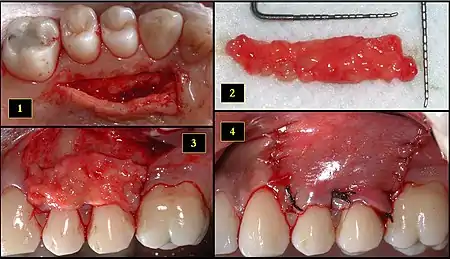

- Recipient site exhibits gingival recession on both premolars and first molar (molar recession is not an esthetic issue and will not be treated)

- Incisions prior to flap reflection

- Full thickness flap elevated

- Another viewpoint of the flapped recipient site

- Ipsilateral palatal mucosa serving as the donor site

- The retrieved connective tissue, approximately 25 × 6 mm in dimension

- Connective tissue placed at recipient site

- Recipient site flap coronally advanced and sutured to entirely cover the graft